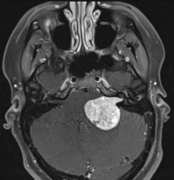

听神经瘤 是一种良性的,通常生长缓慢的肿瘤,由供应内耳的平...